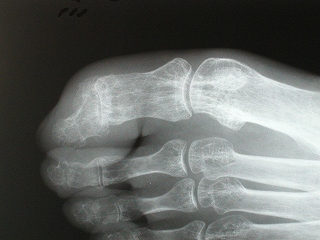

左環指末節骨骨折レントゲン写真 有限会社 土屋広告デザイン研究所

左環指末節骨骨折 有限会社 土屋広告デザイン研究所